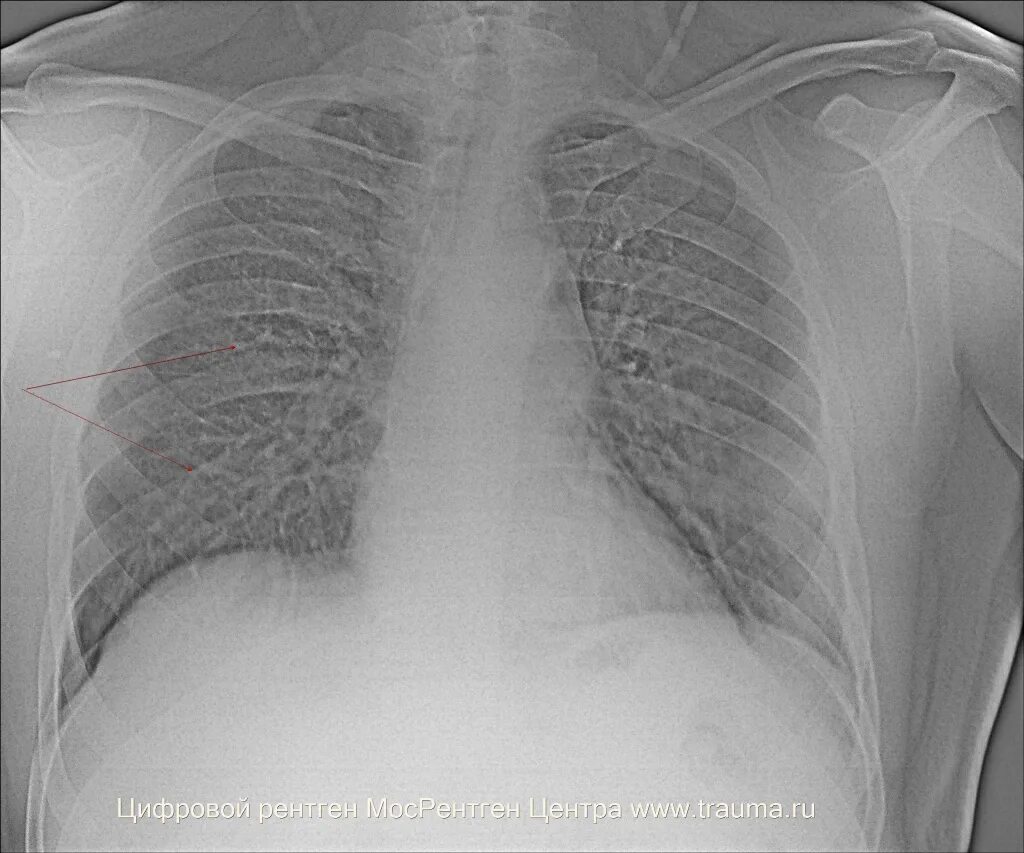

Ээд легких